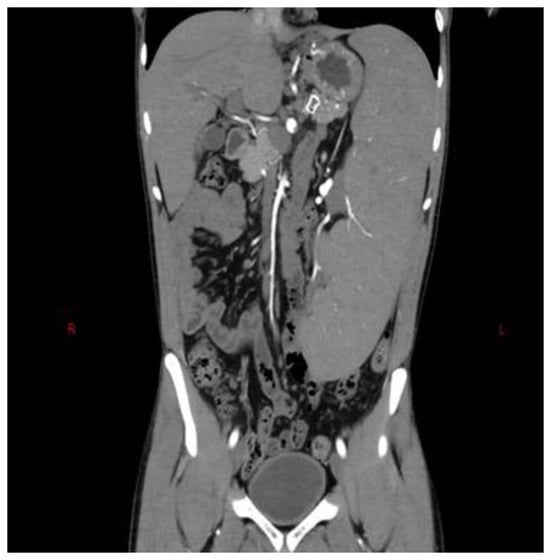

We report the case of a 34-year-old male patient suffering from IPH with splenomegaly and thrombocytopenia (70,000/mm3). He underwent selective embolization of the lower pole of the spleen without post-procedure complications. At one-month follow-up, there was an increase in number of platelets (/mm3) as well as a reduction in spleen volume (Figure 3).

Figure 3.

Super-selective catheterization of the inferior branches suppling the lower pole of the spleen (A) and post-embolization computer tomography (B) in patient with NCPH. The branch leading to the inferior pole of the splenic artery was selectively catheterized with a microcatheter and then embolized with coils of appropriate diameter. The branches leading to the upper lobe have been preserved.